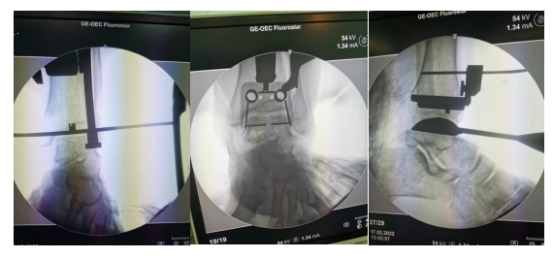

经过详细的术前分析,王文波教授、张涛副教授团队为李女士成功实施右侧全踝关节置换术,术中准确定位并置入踝关节假体,在成功松解软组织的同时又避免了血管神经结构的牵拉破坏,同时采用合适的假体,确保踝关节的稳定性,整个手术过程患者生命体征平稳。术后一周,患者康复出院。

术后复查X线提示右侧人工踝关节置换术后,假体未见松脱、移位及断裂